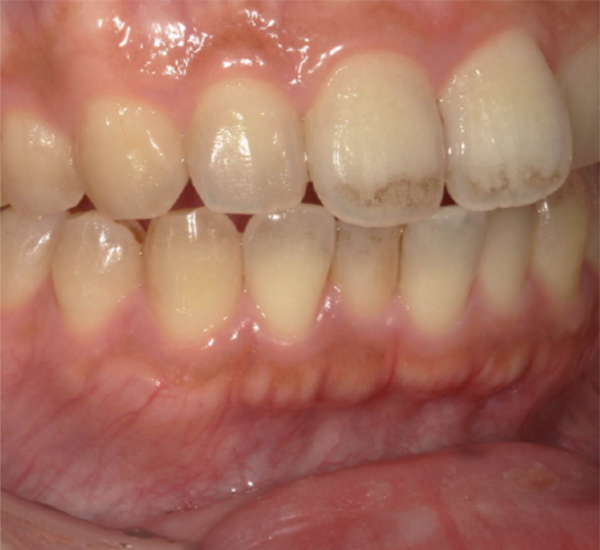

歯みがき粉をかえたら着色が目立ってきた症例

治療前

| 相談内容 | 「この頃着色が目立ってきました。」とご相談いただきました。 |

| 年齢・性別 | 40代 男性 |

| カウンセリング・診断結果 | 定期検診で拝見していた患者さんで、着色もなく虫歯予防も行き届いていました。 普段からお茶を飲まれる方でしたが急に着色するようになってきていましたので、お尋ねしたところ「歯周病予防の歯みがき粉にかえた」とのことでした。 歯周病予防の商品は低研磨の商品が多く、お茶をよく飲まれる患者さんでは着色除去力が足りないことが予想されます。 |